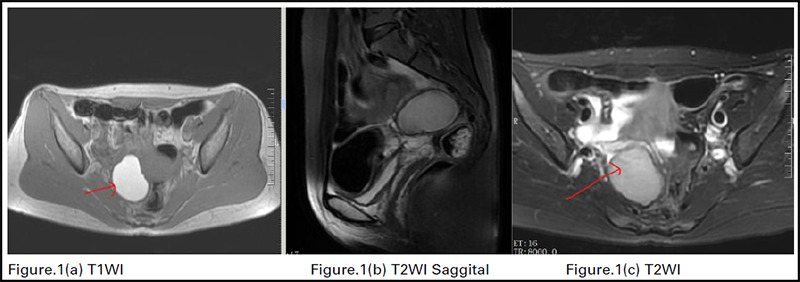

The presence of endometrial tissue outside the uterus is a defining characteristic of endometriosis, a chronic systemic illness that affects women of childbearing age. Despite its enigmatic nature, laparoscopy remains the gold standard for diagnosis, while noninvasive methods such as transvaginal ultrasonography and magnetic resonance imaging are commonly used to aid in preoperative planning. In healthcare, AI has emerged as a game-changing innovation, enhancing patient outcomes, reducing costs, and revolutionizing healthcare delivery, particularly in diagnostic radiology. Images can be analyzed using machine learning, a pattern recognition method. The machine learning algorithm first computes the image characteristics deemed significant for making predictions or diagnoses about unseen images.